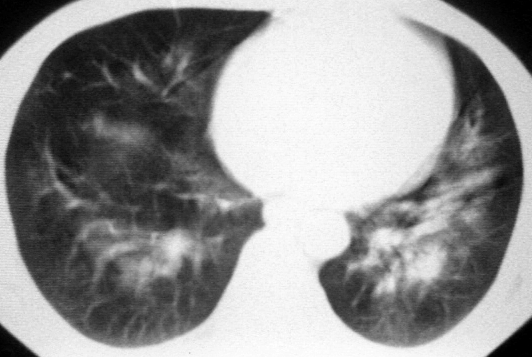

双肺内中部见略不对称性蝶翼状高密度区,边界不清,部分呈磨玻璃样密度,并可见含气支气管征。肺门、纵隔内未见肿大淋巴结影。无胸腔积液。

考虑:1、肺炎,建议进一步查冷凝集试验除外支原体肺炎;

2、不除外霉菌感染。

双肺斑片状密度均匀病灶,边界模糊可见充气支气管征,上野多于下野,不支持结核,1肺内感染,2查肾功,中心型肺水肿待除外.

单从影象学表现考虑肺水肿

影象学表现考虑肺水肿,

符合肺水肿表现,请临床进一步检查。

还是考虑肺水肿!蝶翼征.肺门增大,肺血管影增粗,!!病变累及中内带为主!要排外支原体感染.